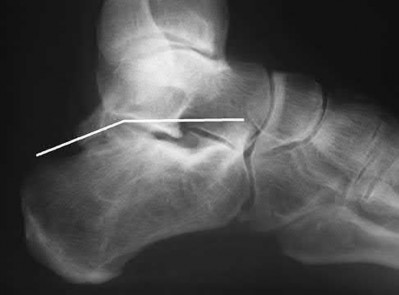

When placing an intramedullary nail for closed distal tibia shaft fractures, all of the following methods are described techniques to aid anatomic reduction EXCEPT:

Of the choices above, syndesmotic fixation would not help anatomically reduce these fractures.

Fractures of the distal tibia are challenging fractures to achieve an anatomic reduction. The medullary canals at either end of the tibia are capacious compared to the mid-diaphysis thus inhibiting an endosteal fit. These fractures have a tendency to become mal-aligned unless certain steps are taken to ensure restoration of the length, alignment, and rotation. Using a Poller or blocking screw can function to narrow the space available for the nail to guide the nail or correct deformity. The use of large pointed-reduction forceps or a small frag plate may also be used for provisional fixation. Additionally, plating concomitant fibula fractures may help indirectly restore length and reduce the tibia fracture. Concomitant syndesmotic injuries are not commonly seen and fixation for these is not required unless stress exam clearly demonstrates it.

Illustration A shows a fibula fracture that was plated prior to tibia IMN placement. Illustrations B and C show the use of pointed reduction forceps placed percutaneously to reduce the fracture. Illustration D shows the use of a blocking screw (denoted by the arrow) to keep the nail lateralized and the fracture out of valgus. Illustration E shows the use of a plate to reduce the fracture prior to nail placement.